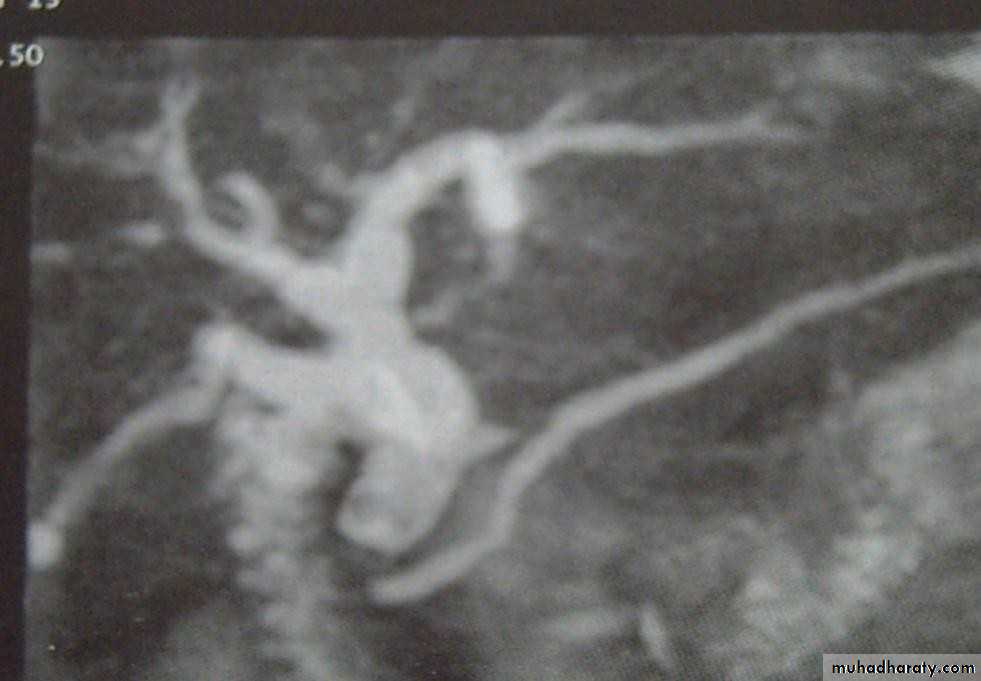

•  Magnetic Resonance Cholangiopancreatograph:

• (MRCP)

•  Standard for biliary tree investigation

•  Contrast is not needed

• MRCP

• Magnetic resonance cholangio- pancreatography crosssectional

• image demonstrating a hilar mass (thick

• arrow) and gallstones (thin arrow)